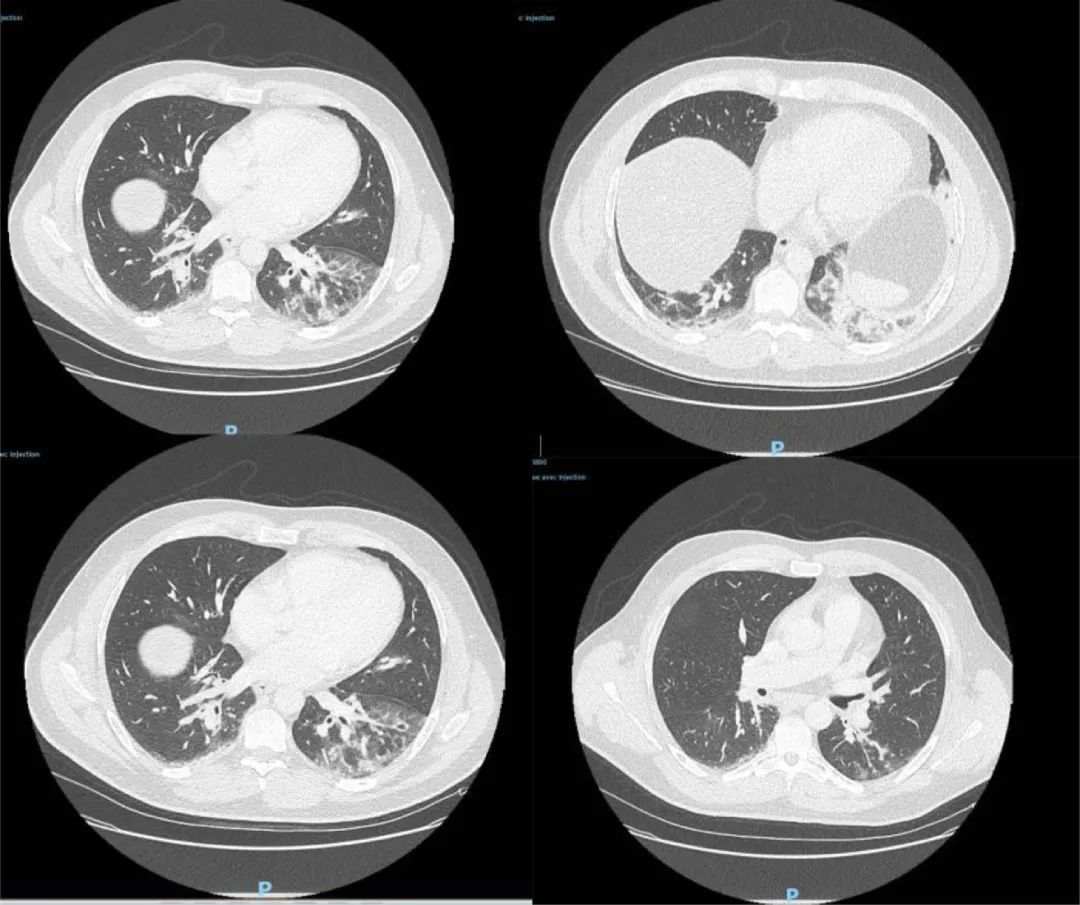

この男性はアルジェリア生まれの魚販売業(yè)従事者で、フランスに長(zhǎng)年にわたり長(zhǎng)期在住しており、2019年8月にアルジェリアへ行ったのが直近の海外渡航歴だった。男性は昨年12月27日に救急治療室で受診し、CT検査の結(jié)果、両方の肺の下葉にすりガラス影が確認(rèn)された。さらに咳や頭痛、発熱癥狀も見られ、しかも受診當(dāng)時(shí)癥狀が4日間続いていた。男性は受診當(dāng)日ICUに収容されて抗生物質(zhì)による治療を受け、後に癥狀が好転して12月29日にICUから一般病棟に移っていた。

△當(dāng)該患者のCT検査畫像